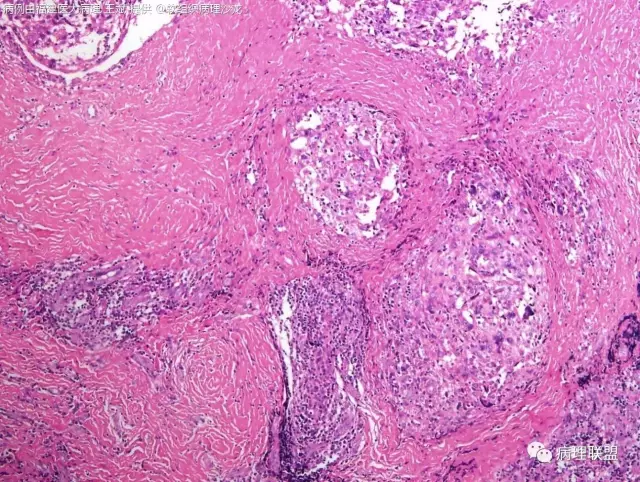

38岁,女性,手部小指背侧皮下肿物,3×2cm(病例由福建医大病理 王斌提供,致谢!)

血管瘤样纤维组织细胞瘤的肿瘤周围有淋巴细胞鞘,结节状分布,有假包膜,出血囊性变的为其主要特点,当然少数病例可以没有出血囊性变却出现粘液变。肿瘤细胞有一定异形性,属于低度恶性或交界性,最好做个FISH,看看有没有EWSR1-CREB1融合基因,刚查了一下,血管瘤样纤维组织细胞瘤还有另一种EWSR1-ATF1融合基因,无论是哪种,用EWSR1分离探针就可以检测